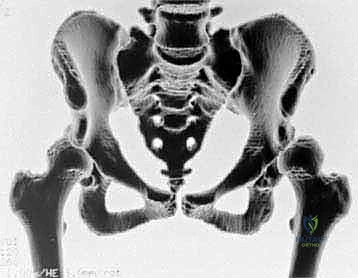

3. التصوير المقطعي المحوسب (CT Scan) ثلاثي الأبعاد: يوفر خريطة طوبوغرافية دقيقة للحوض، مما يسمح للجراح بالتخطيط الدقيق لمقدار وزاوية التدوير المطلوبة للتجويف الحقي.

بمجرد اكتمال هذه القطوع الثلاثة، يصبح التجويف الحقي (الكوب) منفصلاً تماماً عن بقية الحوض، مع بقاء إمداداته الدموية سليمة.

4. إعادة التوجيه والتدوير (Rotation & Redirection)

باستخدام أدوات خاصة، يقوم الدكتور هطيف بتدوير التجويف الحقي الحر في ثلاثة أبعاد (للأمام، وللخارج، وللأسفل) حتى يغطي رأس عظم الفخذ بشكل مثالي وميكانيكي سليم. يتم التحقق من الزاوية الجديدة فوراً داخل غرفة العمليات باستخدام جهاز الأشعة السينية المتحرك (C-arm).